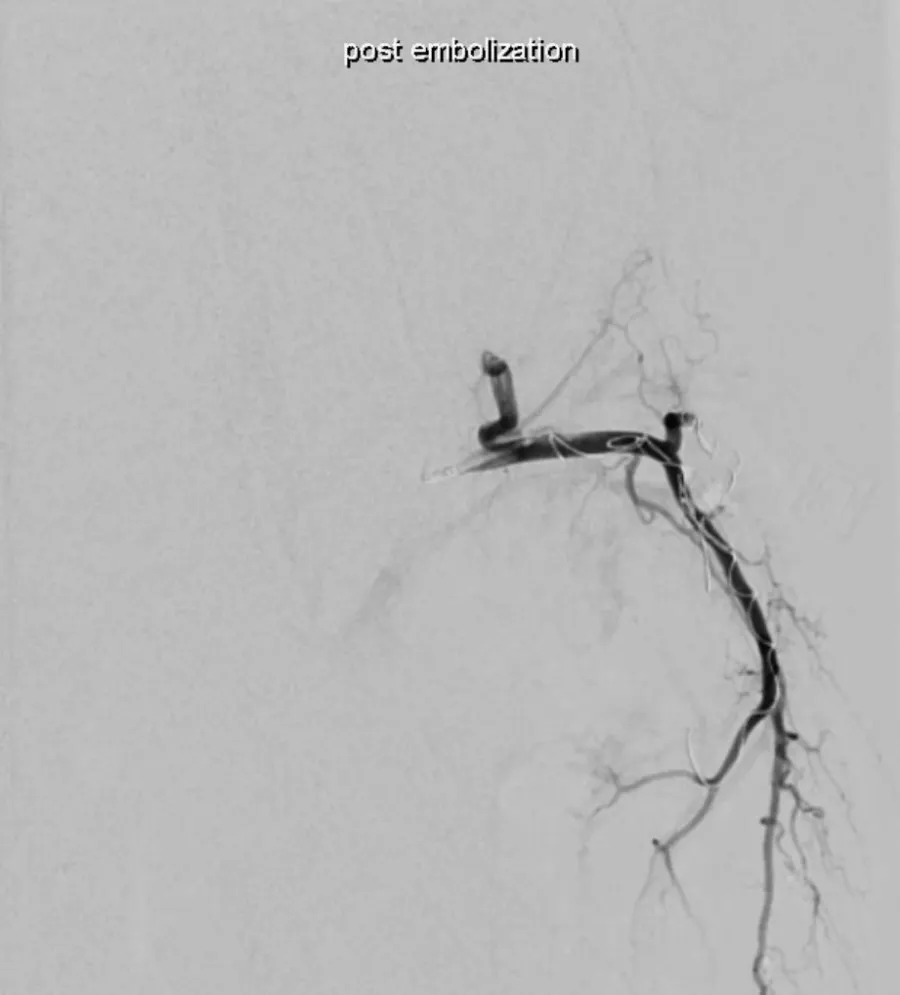

Adequate catheter position attained using the Swift Ninja Catheter by Merit Medical. Final image showing reduced vascularity.